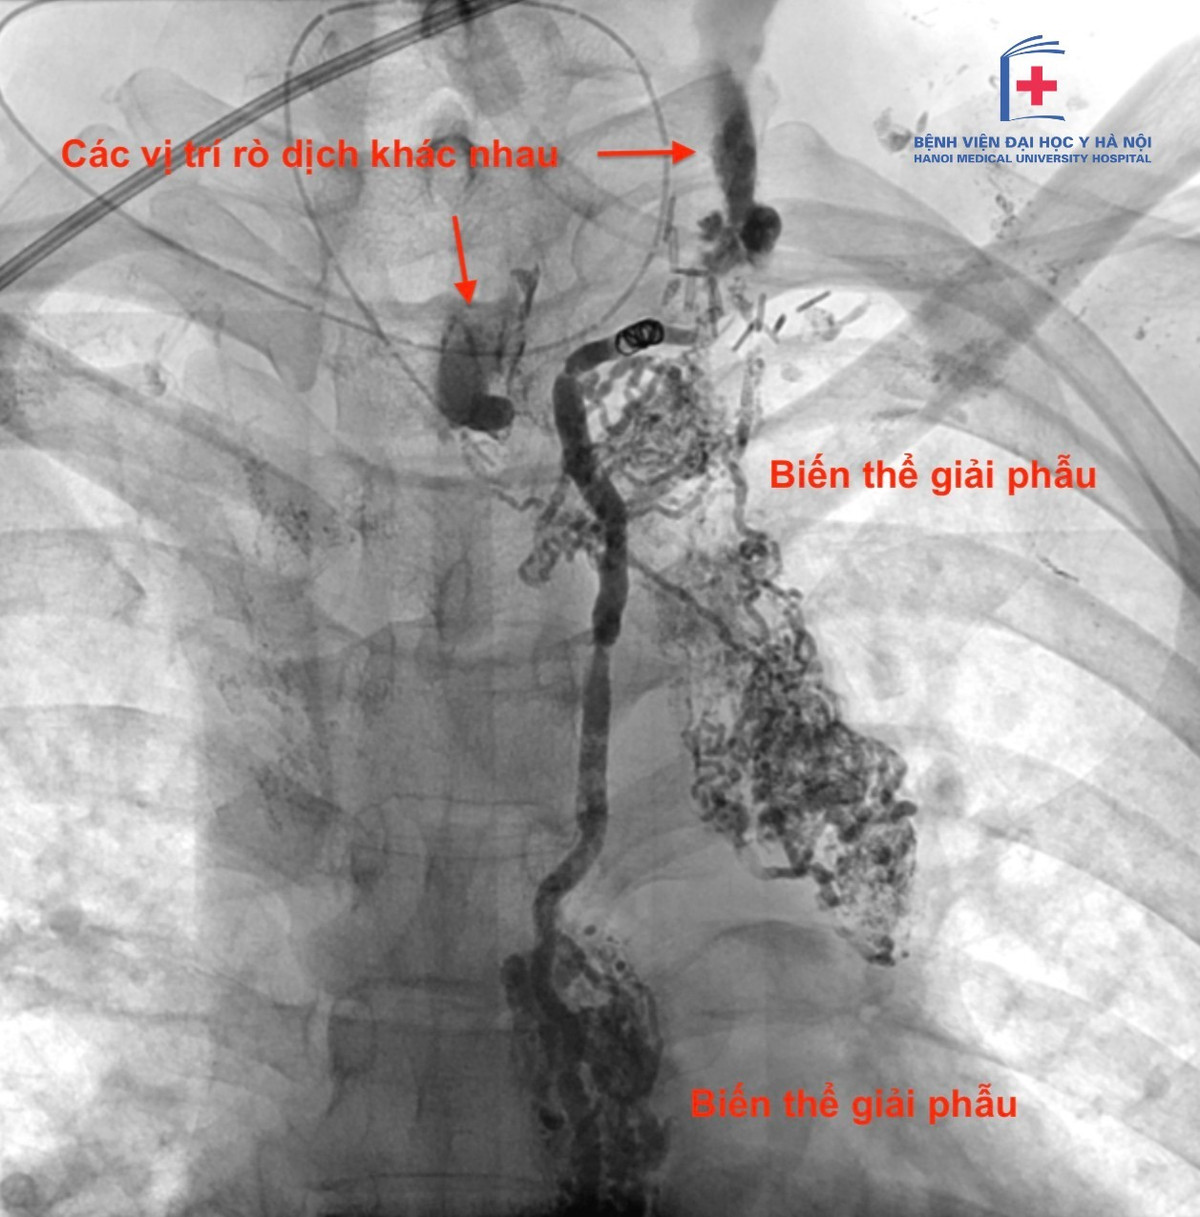

Theo TS.BS Nguyễn Ngọc Cương, Trưởng khoa Can thiệp điện quang, Bệnh viện Đại học Y cho biết: Rò dưỡng chấp không hoàn toàn phản ánh kinh nghiệm phẫu thuật hay mức độ xâm lấn của khối u. Trong nhiều trường hợp, nguyên nhân xuất phát từ biến thể giải phẫu vốn có của người bệnh.

Ở trường hợp kể trên, bệnh nhân có cấu trúc ống ngực với nhiều nhánh bàng hệ nhỏ tại vùng cổ. Chỉ cần tổn thương một vài nhánh li ti trong quá trình phẫu thuật cũng có thể dẫn đến rò dưỡng chấp, dù thao tác kỹ thuật vẫn được thực hiện đúng chuẩn.

ro-duong-chap-1.jpg

Dịch rò dưỡng chấp trên phim chụp - Ảnh BVCC